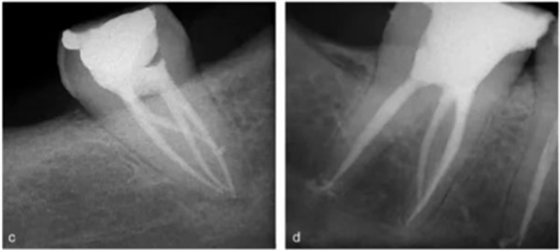

一般來說,遠(yuǎn)舌根比遠(yuǎn)頰根和近中根小,可能獨(dú)立于或部分融合于其他牙根。臨床治療過程中,當(dāng)懷疑存在額外的牙根時(shí),需要根據(jù)準(zhǔn)確的放射學(xué)診斷、臨床檢查、開髓洞型預(yù)備進(jìn)行判斷。在術(shù)前的放射片中,若遠(yuǎn)中根輪廓或根管的視野或外形不清楚,可能表明存在“隱藏的”牙根。在近中或遠(yuǎn)中成 30 度角的方向上拍攝第二張放射片,通常可以顯示遠(yuǎn)舌根的輪廓。

使用牙周探針對(duì)牙冠或牙頸部形態(tài)進(jìn)行臨床檢查有助于發(fā)現(xiàn)額外的牙根。一個(gè)額外的牙尖(副磨牙結(jié)節(jié),tuberculum paramolare)或明顯突出的遠(yuǎn)頰或遠(yuǎn)舌小葉,伴有頸部的突出,可能表明存在額外的牙根。遠(yuǎn)舌根的根管口位于主要的遠(yuǎn)中根管的近舌側(cè),因此開髓洞型需要預(yù)備成矩形或梯形。使用牙髓探針仔細(xì)檢查髓室底的暗色的發(fā)育溝,可以精確的定位遠(yuǎn)舌根根管口。

使用手術(shù)顯微鏡是非常有幫助的,特別是在那些根管口被鈣化物覆蓋的病例中,這些鈣化物可以使用超聲尖或長(zhǎng)柄小球鉆輕松去除(圖 14a-d)。